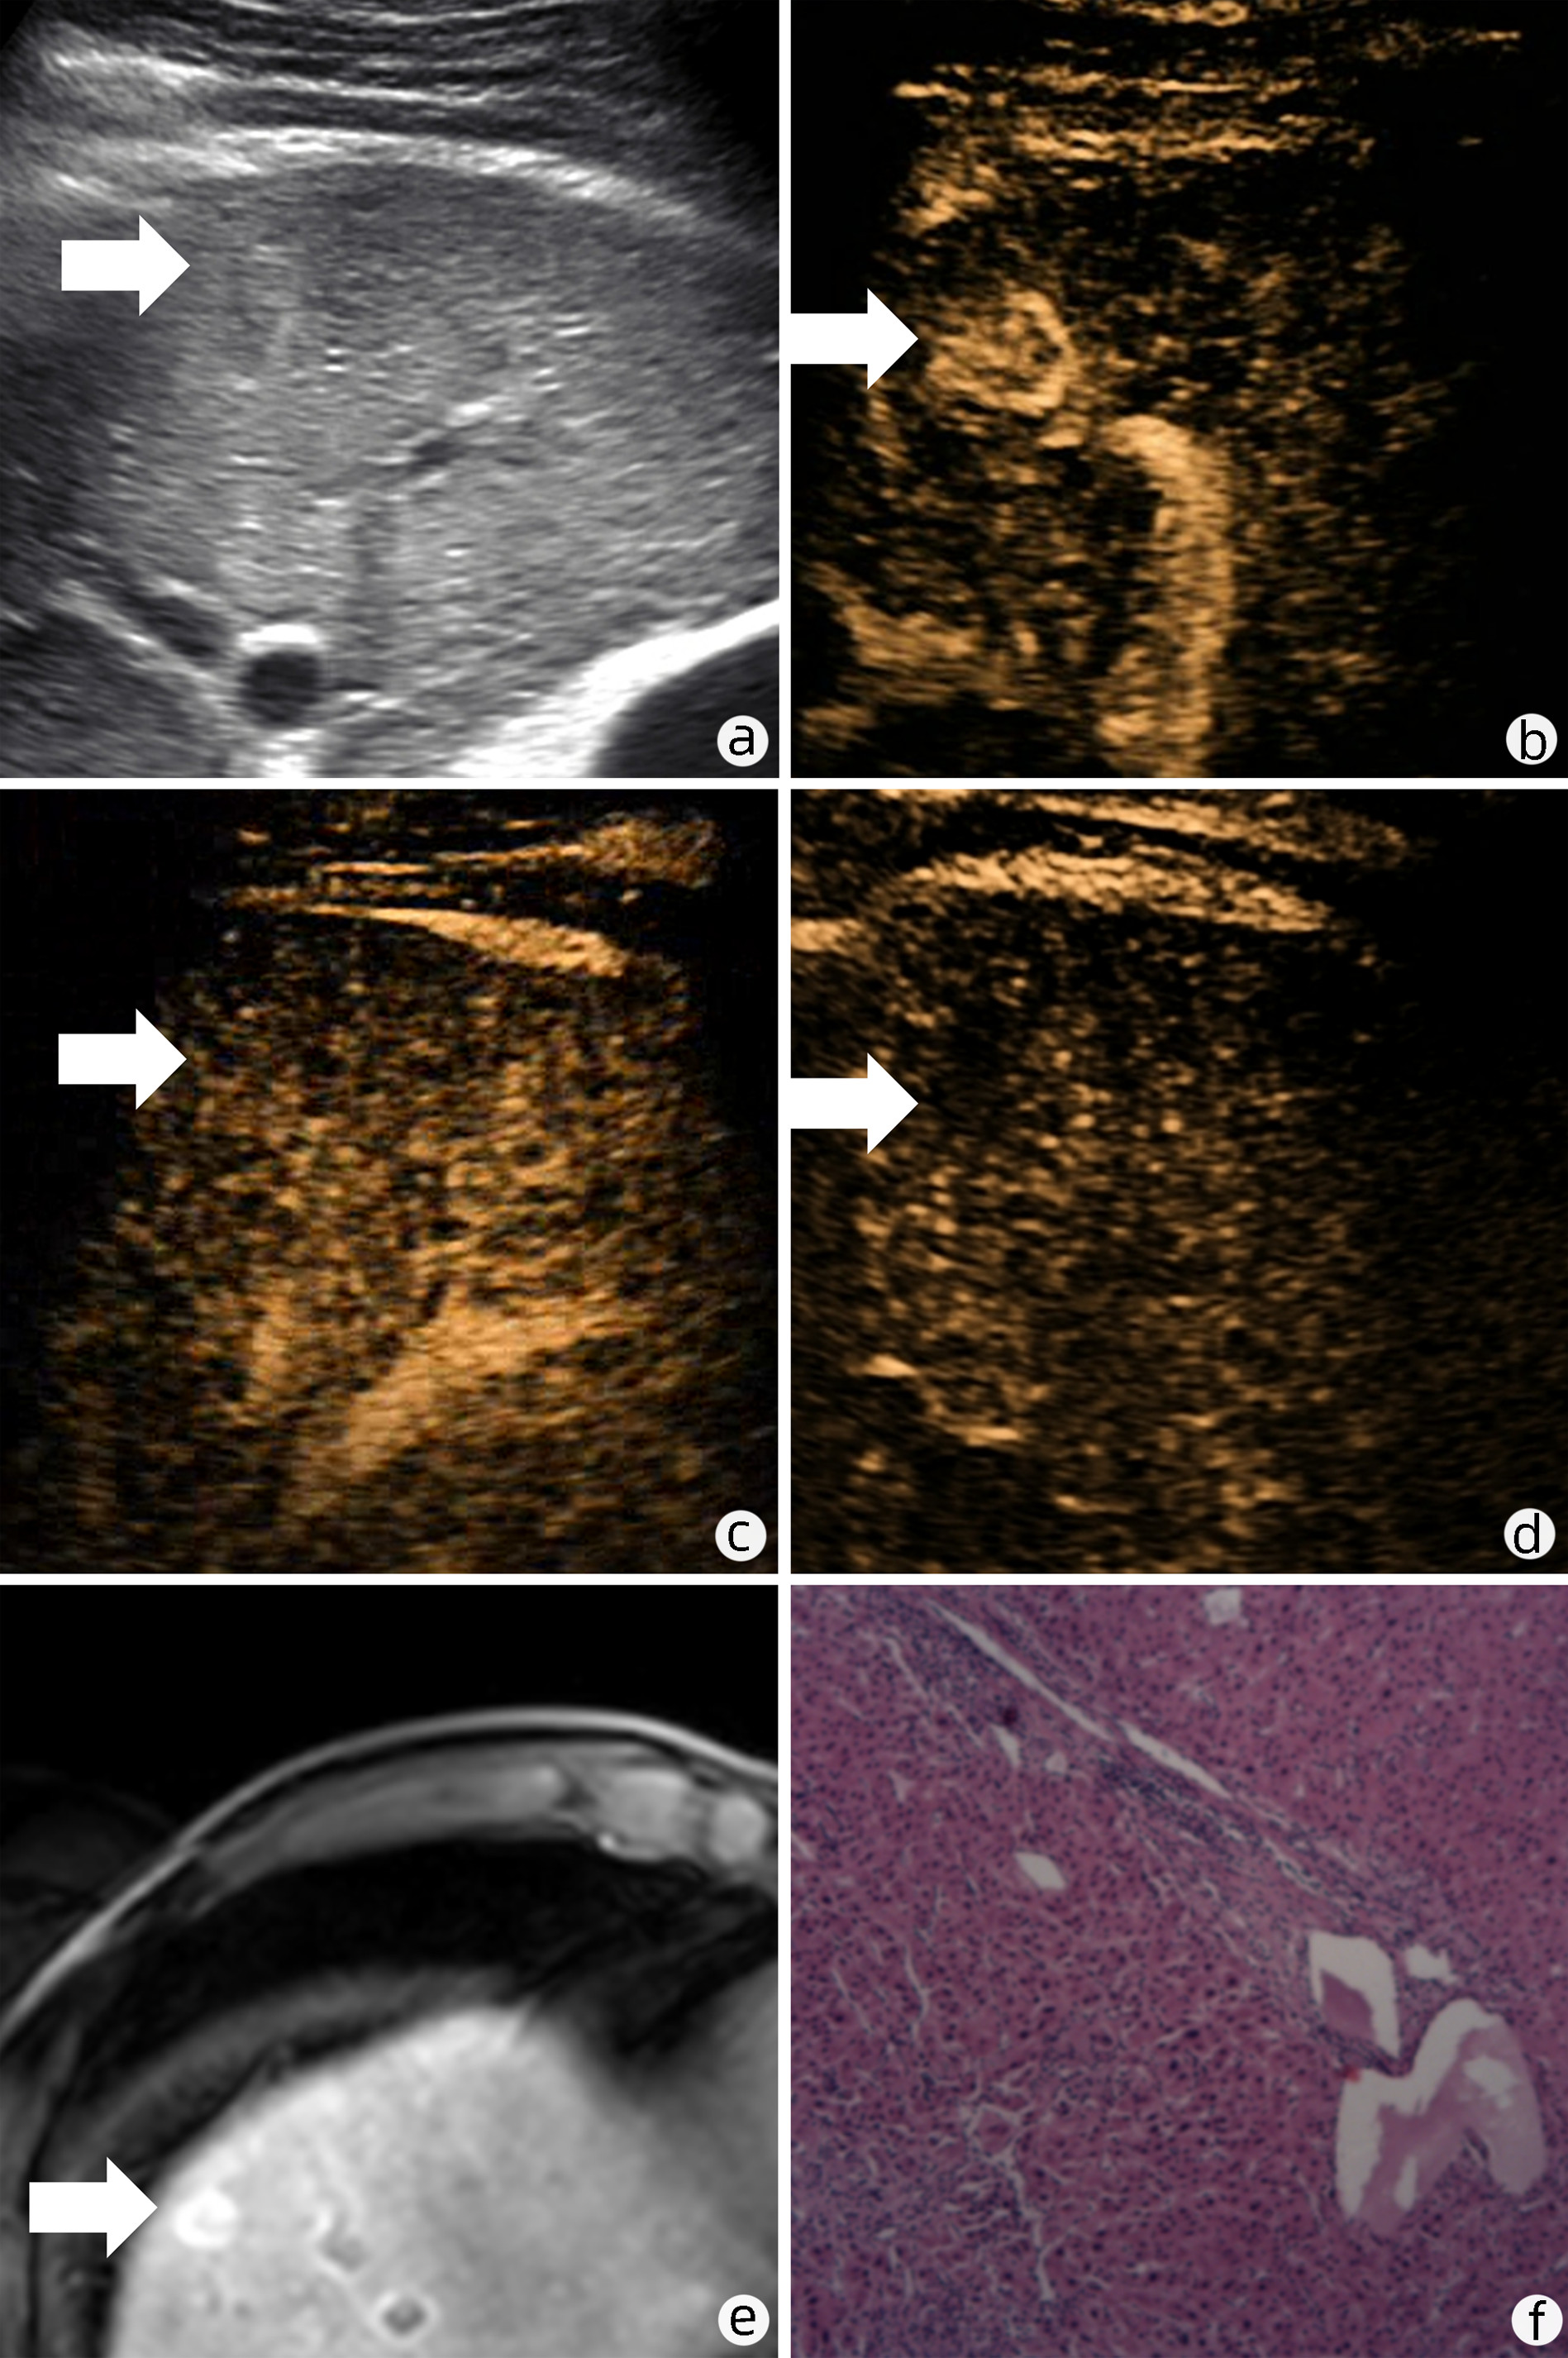

Focal nodular hyperplasia-like nodules in liver cirrhosis: An imaging analysis of three cases